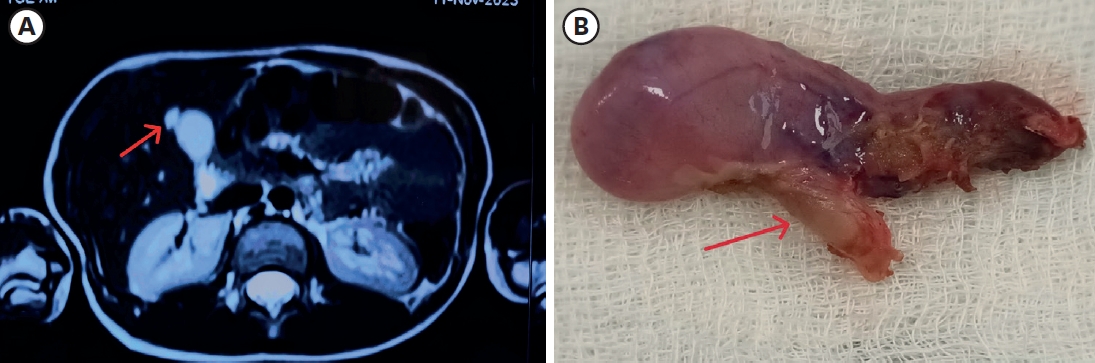

Hirschsprung Disease Associated With Pelvic Neuroblastoma: A Rare Neurocristopathic Association

Sravanthi Vutukuru, Nitin J Peters, Shailesh Solanki, Amita Trehan, Kirti Gupta, Monika Bawa

Adv Pediatr Surg 2024;30(1):32-37.   Published online January 29, 2024

DOI: https://doi.org/10.13029/aps.2024.30.1.32

Hirschsprung disease (HSCR) is a genetic disorder with an incidence of 1:5000, seen in the pediatric age group. The association between HSCR and neuroblastoma (NBL), ends of the neurocristopathy spectrum is rare. Less than 10 cases of this association are reported in the literature and the association between the Phox gene and Sox10 gene in the pathophysiology of these is being studied. We report a one-year-old baby, who presented to us, with chronic constipation on regular enemas and laxative usage. There was a history of delayed passage of meconium. At the time of Duhamel’s pull through a well-defined, bilobed hard presacral mass, was encountered. Excision and coccygectomy were done and the pull was completed. The histopathology showed a well-differentiated NBL. Fludeoxyglucose positron emission tomography scan and the N-Myc amplification were negative and the patient was managed with expectant treatment. She is doing well over a 3-year follow-up with no recurrence and good resolution of bowel functions.